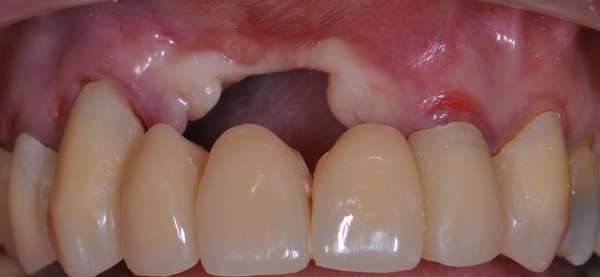

O defeito vertical severo do rebordo maxilar anterior representa um dos cenários clínicos mais desafiadores da regeneração óssea. Portanto, para obter resultados satisfatórios, é necessária uma abordagem precisa, por meio da combinação de aumento ósseo vertical e manipulação de tecidos moles. Aqui, será descrita uma técnica para tratar deficiências verticais severas na maxila atrófica anterior (Figuras 1) usando membrana de politetrafluoroetileno denso (PTFE-d) e enxerto ósseo particulado heterógeno. A manipulação do tecido mole deverá ser utilizada para superar as desvantagens do aumento vertical do osso (por exemplo, perda da profundidade vestibular e mucosa queratinizada).

Entretanto, é de suma importância a correta e precisa abordagem cirúrgica, no que tange à incisão do rebordo alveolar. Nesse procedimento, foi realizada uma incisão “invertida”, que seria uma modificação da técnica de Kazanjian1. Uma incisão labial foi realizada perto do limite do vermelhão do lábio (Figuras 2 e 3), produzindo um retalho de base palatina, o que é indicado sempre que há necessidade de aumento substancial na altura do rebordo maxilar anterior (Figuras 4 e 5).